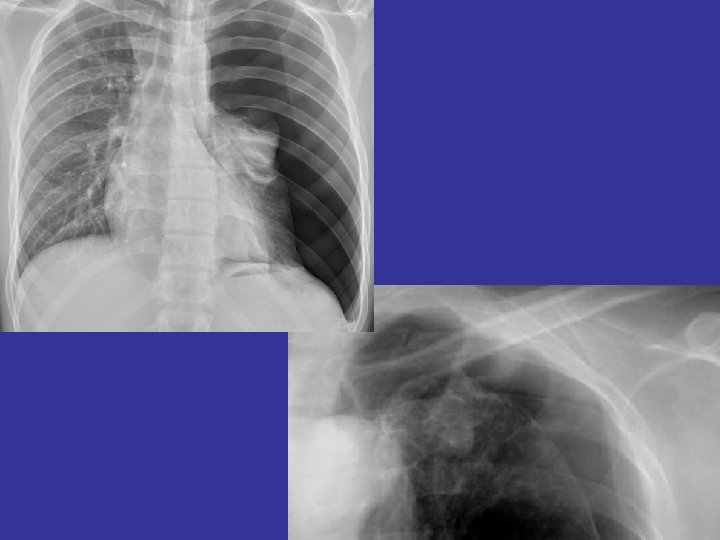

• 1. Physical examination / Vital signs Inspection jugular vein trachea respiratory muscle

• 1. Physical examination / Vital signs Inspection jugular vein trachea respiratory muscle Auscultation breathing sound heart sound • 2. Image study 2021/10/24 4